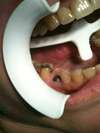

Mise en place du pilier